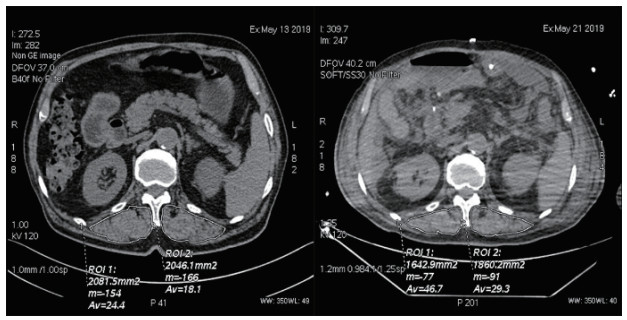

1.3 研究方法 1.3.1 胸部CT扫描和竖脊肌横截面积测量分析所有纳入患者在入院前或入院首日即行胸部CT扫描检查,并于治疗7日后复查胸部CT,在胸部CT应用纵隔窗进行竖脊肌横截面积分析。定位T12椎体下缘水平分析竖脊肌[9]。详细记录竖脊肌横断面面积测量结果,在CT图像上识别左右竖脊肌,并手动勾画竖脊肌伪彩,计算两边竖脊肌横断面积和脊柱左右竖脊肌总的横断面积,见图 1。

| 图 1 同一患者竖脊肌横截面积测量及对比 Fig 1 Measurement and comparison of cross-sectional area of erector spinae in the same patient |